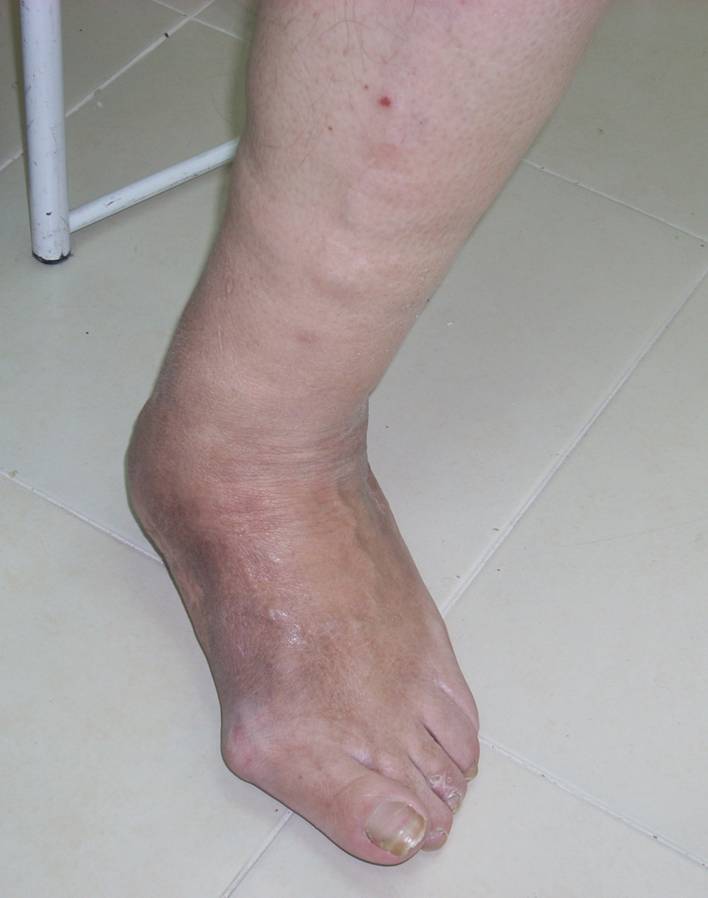

A 63-year-old male presented to the authors’ clinic at the Shaarei Zedek Medical Center, Jerusalem, Israel with a red, hot, swollen foot and ankle, with a severe pronation deformity (Figure 1). On examination the patient was standing and ambulating on the medial aspect of his foot and had developed a University of Texas Diabetic Wound Classification 1A ulceration on the medial aspect of the foot over the navicular bone. In addition, there was small sterile blistering of the skin in multiple areas (Figure 2). The ankle, subtalar, and midfoot joints were found to have excessive movement attributed to the underlying joint destruction. A diagnosis of active development phase of Charcot foot was given.

After 4 months of casting the patient was able to utilize a straight last, lace-up boot. The patient was followed for 36 months after the procedure and had full ambulation with a plantigrade foot and generally stable epithelium without consequence of new wounds while wearing only his customized boots (Figure 5). Figure 6 shows a current x-ray taken just before publication of this report, and Figure 7 shows the patient standing.